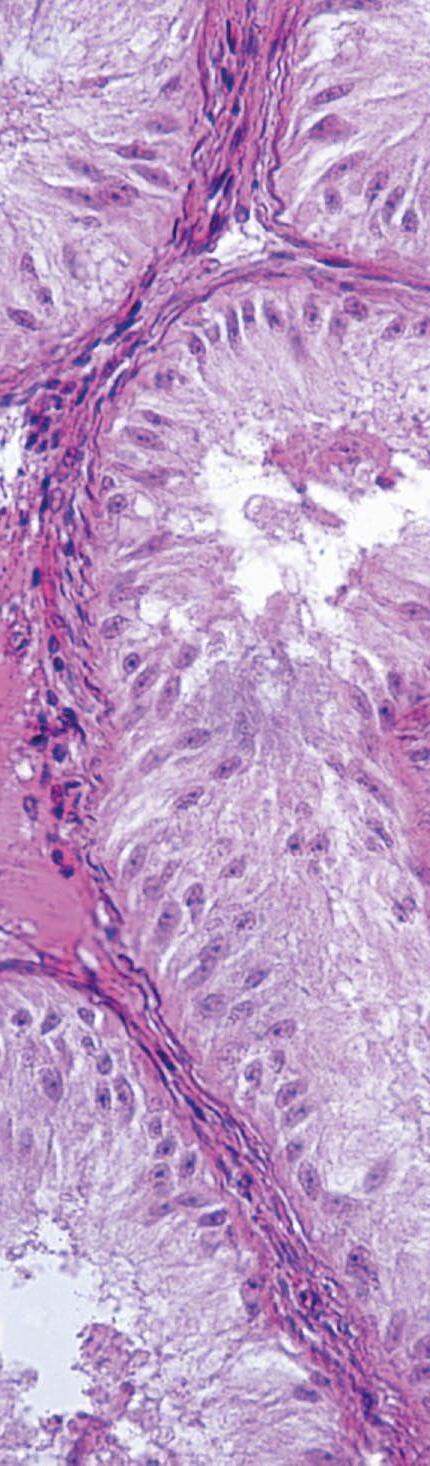

FIGURA 2

Microfotografía que muestra la interfase materno-fetal en el día 45 de gestación en cerdas (Tinción con hematoxilina-eosina (HE)). (1) Membrana corioalantoidea – pliegue primario, (2) Membrana corioalantoidea – pliegue secundario, (3) Endometrio – pliegue primario, (4) Endometrio – pliegue secundario, (5) Glándula endometrial y (6) Vasos uterinos (Reis, 2021).